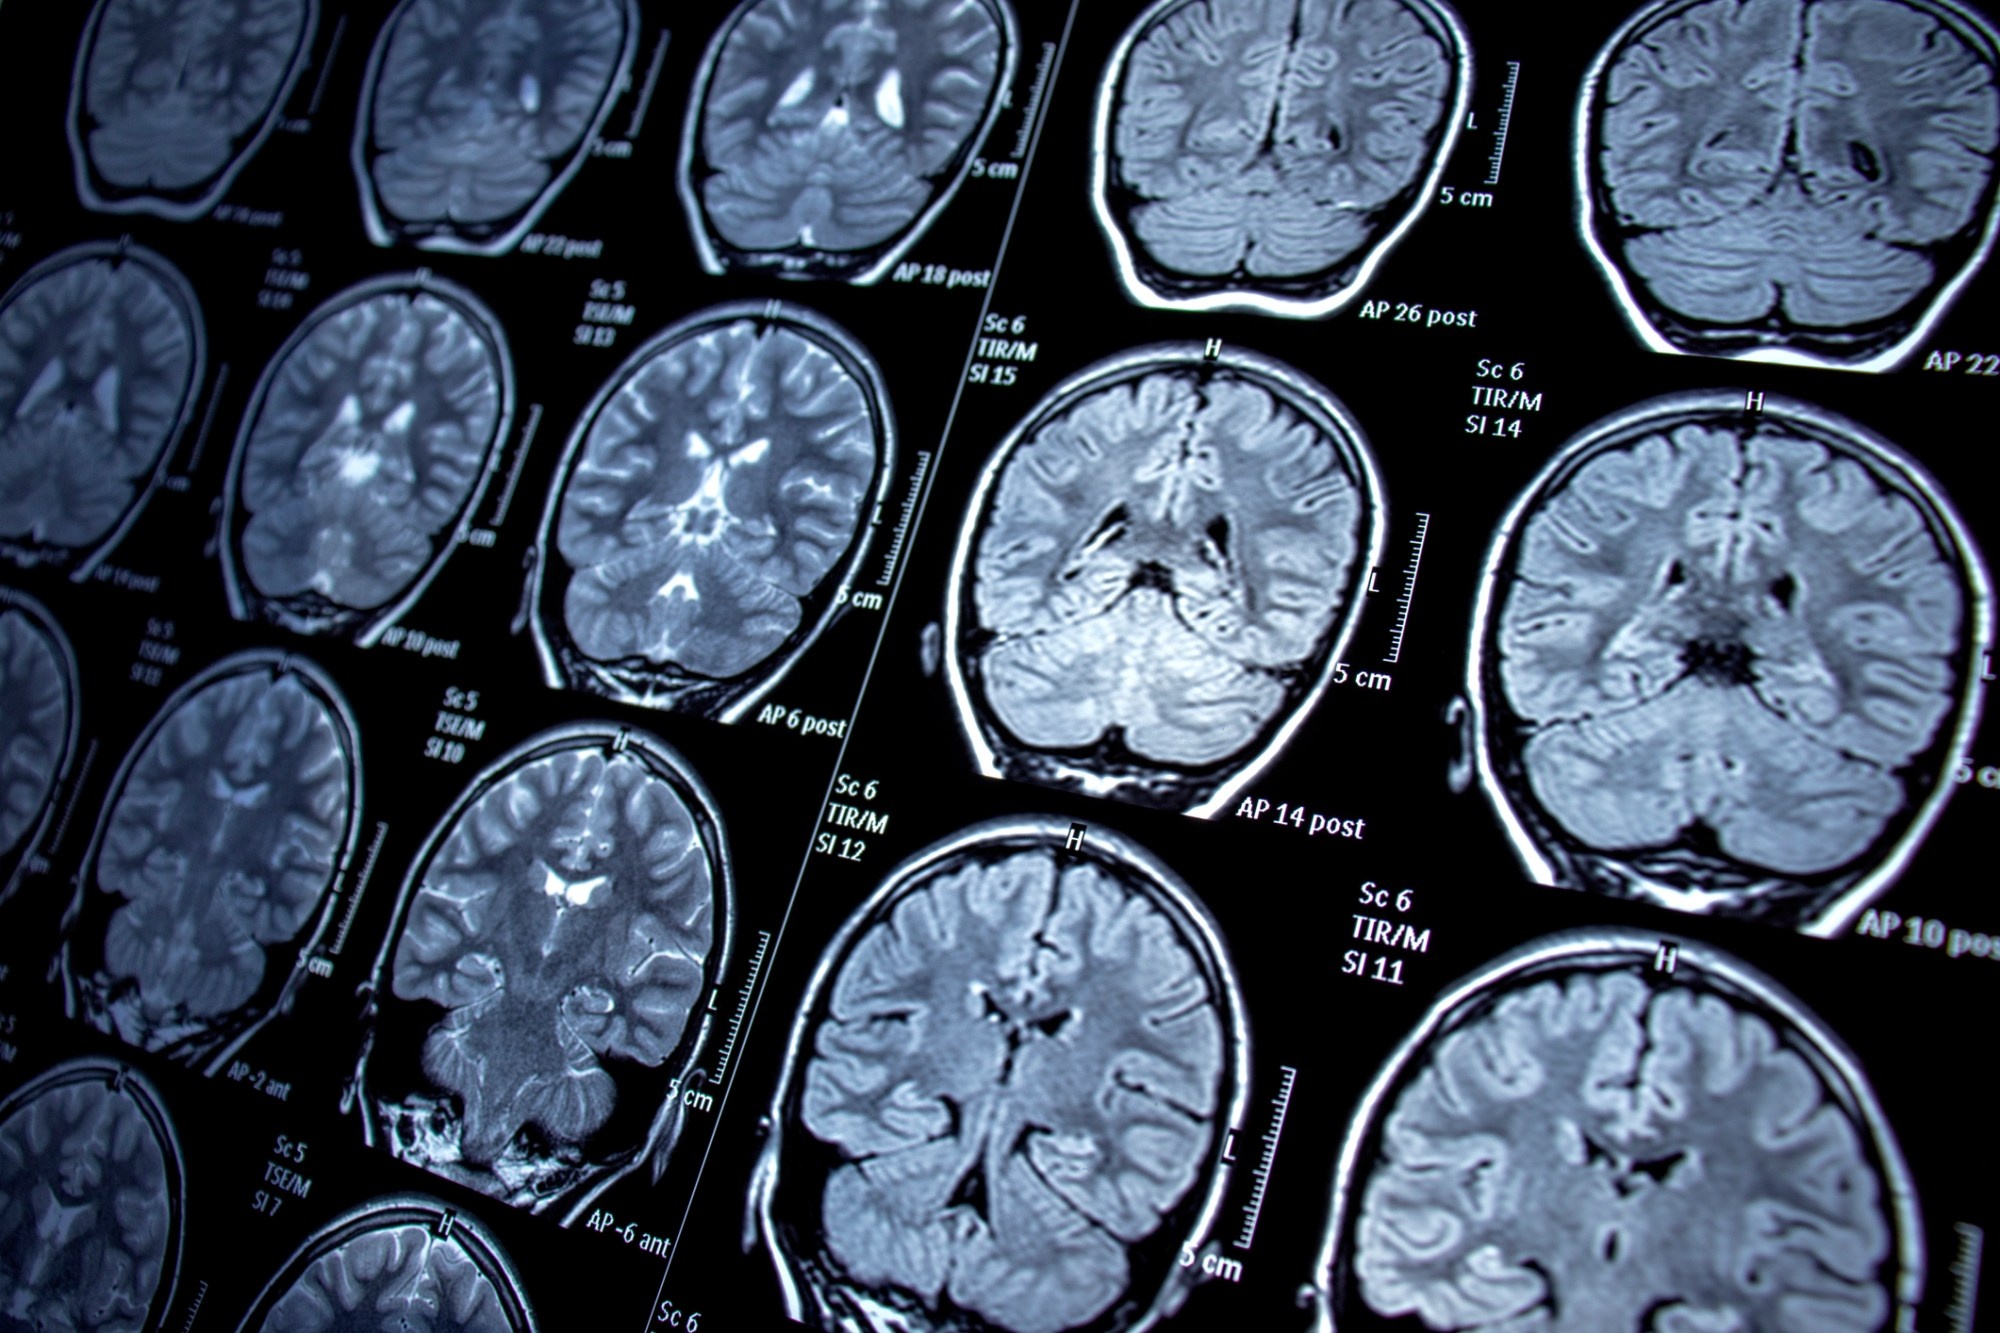

Do đã được điều trị khỏi Covid-19 vài tuần trước đó và có kết quả xét nghiệm khẳng định bằng phương pháp rRT-PCR, các bác sĩ nghi ngờ nguyên nhân tử vong là di chứng Covid-19.